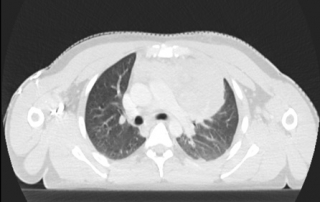

Examen clinique : adénopathie sus-claviculaire gauche, présence de sueurs nocturnes depuis un mois.

Hémogramme : hémoglobine 11.2 g/L, GB 7.9 G/L, lymphocytes 1.4 G/L, albumine 32 g/L, VS 98 mm.

Biopsie d’une adénopathie cervicale: lymphome de Hodgkin classique sclérose nodulaire riche en cellules tumorales.

Fibroscopie bronchique : compression extrinsèque de la lingula, biopsies bronchiques ne montrent pas d’infiltration tumorale.

Stade IV forme thoracique, atteinte médiastinale volumineuse et pulmonaire. Les examens d’imagerie ne montrent pas d’extension sous-diaphragmatique.

| Avant traitement | Après BEACOPP renforcé x 2 cycles Masse médiastinale dont le SUVmax est comparable au bruit de fond hépatique, correspondant à une réponse métabolique complète |

Résultat : la réponse métabolique complète après BEACOPP renforcé 2 cycles conduit à poursuivre le traitement par ABVD x 4 cycles selon l’essai AHL2011, avec évaluation après ABVD 2 cycles et en fin de traitement. La TEP-TDM montre une masse médiastinale résiduelle de taille 36 x 42 mm inchangée entre l’évaluation après 4 cycles et en fin de traitement, avec maintien de la réponse métabolique complète, correspondant à une diminution de 88%. Classement rémission complète incertaine selon les critères de Cheson 1999 et à une rémission complète selon les critères IWG 2007.